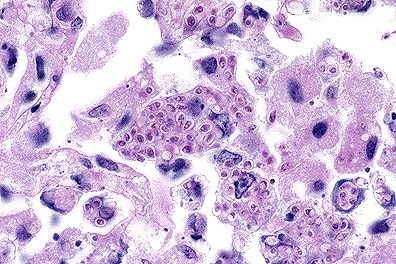

. Pulmonary Yersinia pestis infection in a monkey. (100X, BH, 118K)

Gross Pathology: A severe multilobar pneumonia with serosanguineous pleural effusion and minimal fibrinous pleuritis was present. The multilobar pneumonia was characterized by multiple red, heavy, edematous lobes that failed to collapse. Within the involved lung lobes, there were spherical to discoid necrohemorrhagic foci up to 2 cm in diameter.

1. Lung: Pneumonia, necrohemorrhagic and suppurative, focally extensive, moderate with intralesional bacilli.

2. Lung: Pneumonia, fibrinosuppurative, multifocal, mild with intralesional bacilli.

3. Lung: Alveolar flooding, focally extensive, moderate with congestion, minimal acute inflammation, hemorrhage, fibrin, and intralesional bacilli.

4. Lung: Edema and hemorrhage, perivascular, multifocal, mild.

5. Lung, lymphatics: Lymphangitis, multifocal, minimal with intralymphatic bacilli.

6. Lung, pleura: Pleuritis, fibrinous, multifocal, minimal with hemorrhage and intralesional bacilli.

7. Lung, circulating blood: Bacillemia and neutrophilia.

8. Lung, blood vessels: Fibrin microthrombi, multifocal, minimal.

Primary pneumonic plague in humans begins as a bronchopneumonia characterized by numerous bacteria and a proteinaceous effusion in the alveoli. The pneumonia spreads rapidly, becoming lobar, then multilobar, and is accompanied by pleuritis. Microscopic examination reveals hemorrhage, foci of necrosis, numerous bacilli in most of the alveoli, and relatively scant suppuration in comparison to the number of bacteria.

AFIP Diagnosis: Lung: Pneumonia, fibrinohemorrhagic, acute, diffuse, severe, with intra-alveolar edema, and myriad bacilli, African green monkey (Cercopithecus aethiops), primate.